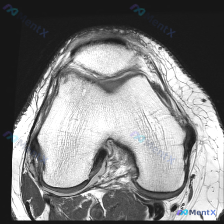

今天看到一个很有代表性的读片问题,整理出来和大家分享讨论:问题是判断这张髌股关节轴位T1加权MRI上有没有软骨异常,我们一步步梳理思路。 一、先看影像基本信息 这是一张膝关节MRI的轴位T1加权图像,扫描层面位于膝关节上方的髌股关节层面: 1. 骨骼结构:髌骨位于前方,骨皮质边缘清晰,骨髓脂肪信号正...

看到这个挺有代表性的读片病例,整理一下资料和分析思路分享给大家。 病例基础信息 这是一份单张膝关节MRI轴位T1加权序列影像,临床怀疑存在软骨异常,要求读片分析。 影像学读片结果 解剖结构评估 1. 骨性结构:髌骨形态完整,皮质连续,骨髓信号无异常;髌股关节对合关系大致正常,无半脱位;股骨远端滑车区...

今天遇到一个有意思的读片问题:只给了一张膝关节轴位MRI,问这里有没有软骨异常,整理一下分析思路分享给大家。 基本病例/影像信息 提供的是膝关节单张轴位MRI扫描图像,可识别的解剖结构包括:前方的髌骨、中部的股骨内外侧髁与髁间窝、髌股关节间隙,以及周围部分软组织。 客观影像所见 1. 软骨结构:髌骨...

看到一个很有讨论意义的膝关节影像病例,整理出来和大家分享一下。 病例基本信息 核心问题:临床怀疑存在膝关节软骨异常,仅提供单张膝关节MRI T1序列轴位影像进行分析。 影像学读片结果 这张影像为髌股关节层面的轴位T1加权像,读片结果如下: 1. 骨骼结构:髌骨、股骨内外侧髁形态完整,皮质骨连续,松质...

最近遇到一个有意思的读片病例:临床怀疑髌股关节软骨异常,但给出的单张T1加权轴位MRI却没看到明确病灶,整理一下整个分析思路分享给大家。 一、病例影像基础信息 这是一份膝关节MRI检查的T1加权轴位(横断面)图像,扫描层面位于髌股关节水平,先整理一下基础读片结果: 1. 解剖结构确认:前方为髌骨,后...